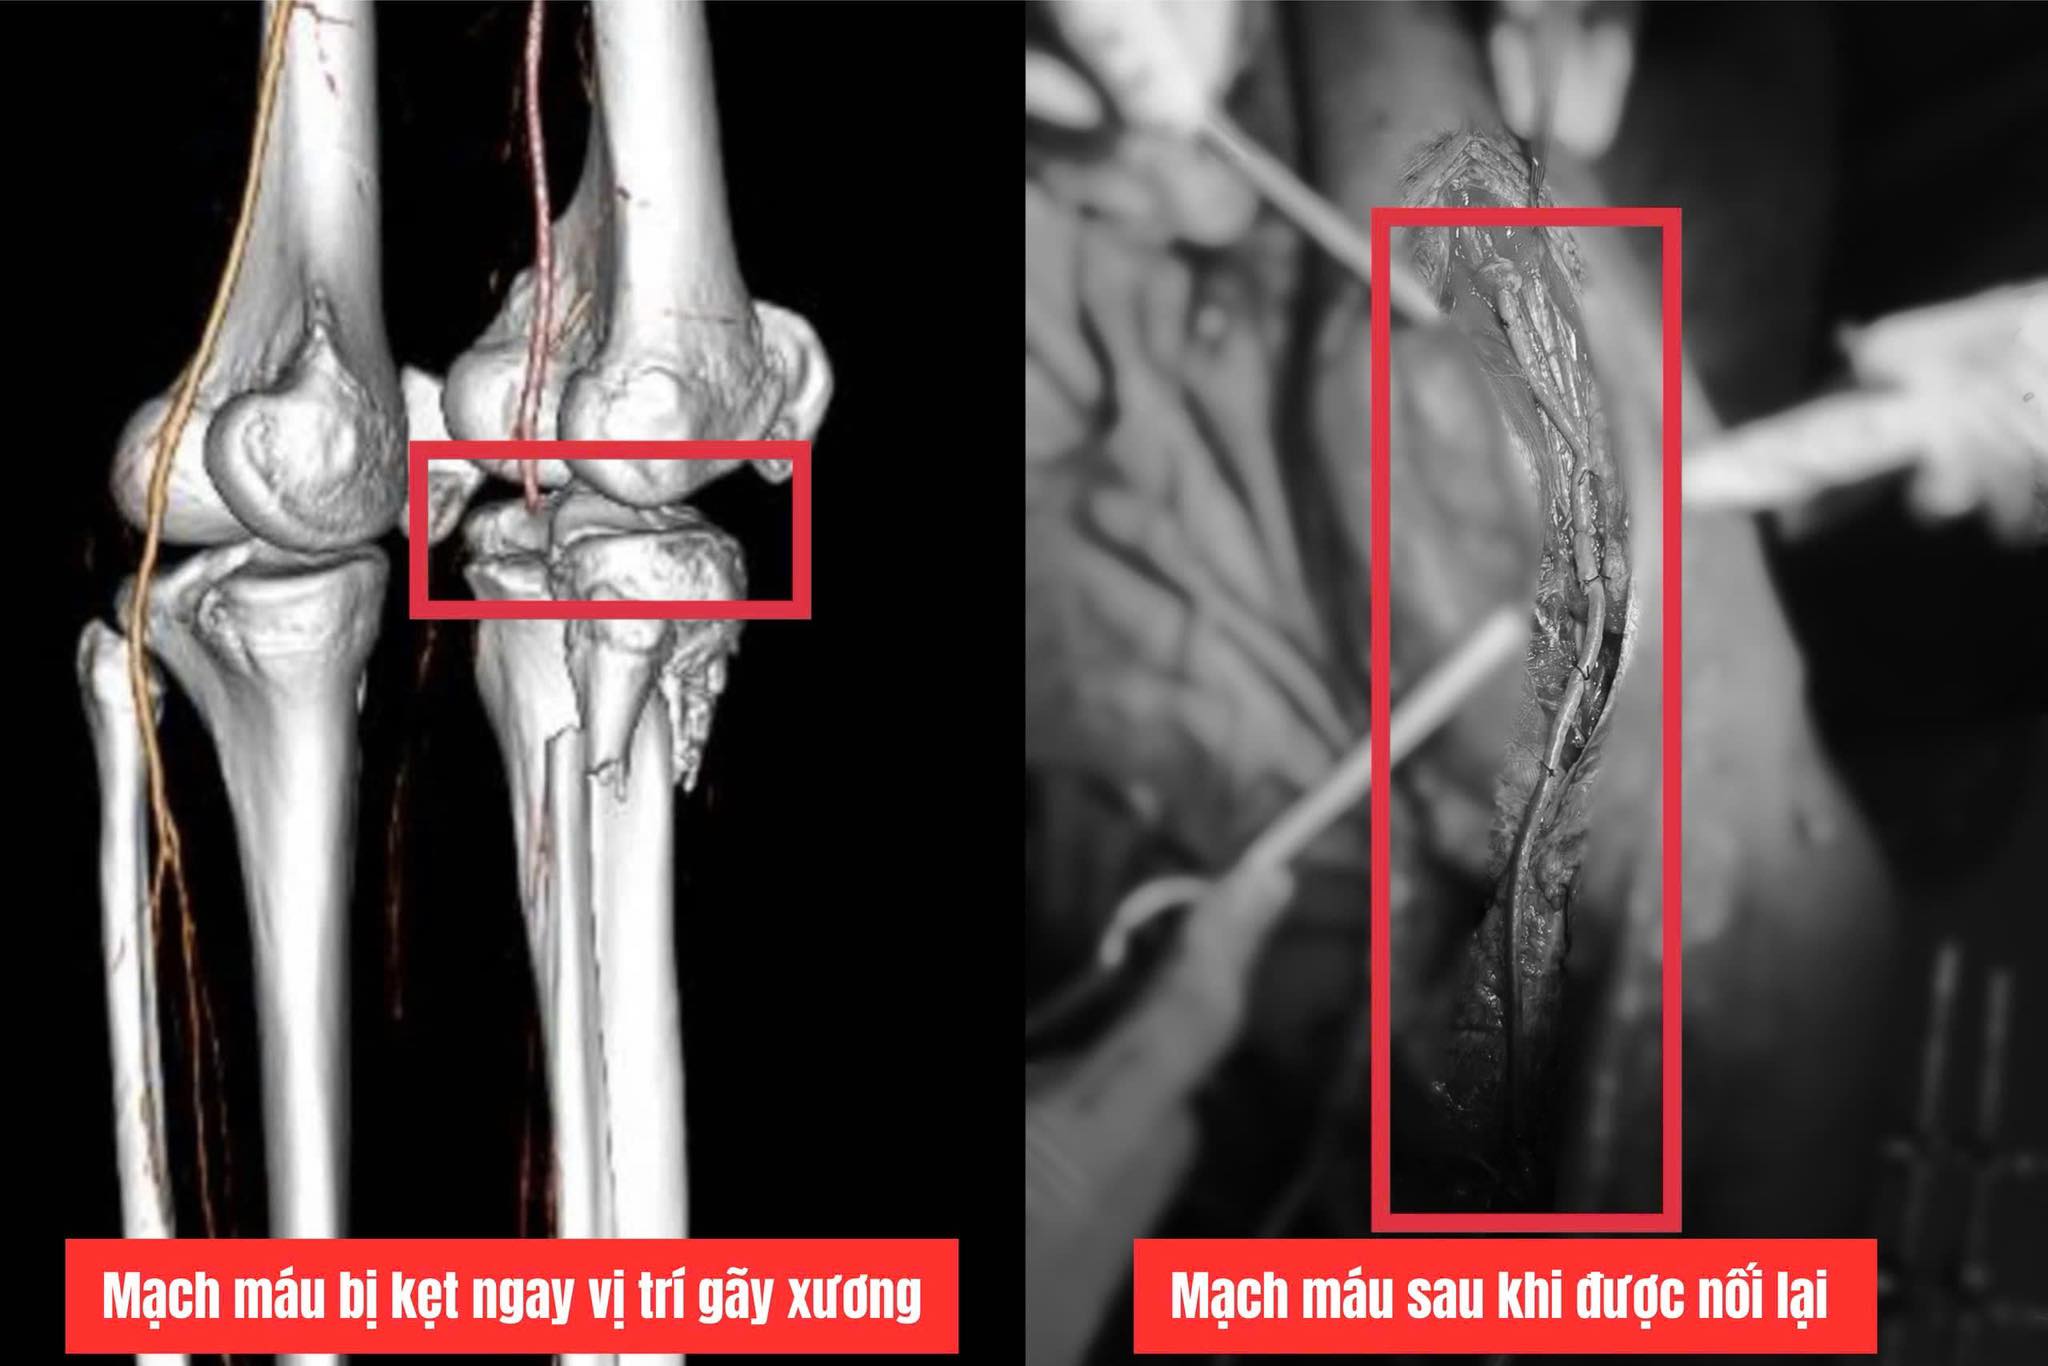

Bác sĩ phát hiện động mạch bị kẹt giữa ổ gãy xương, đoạn động mạch khoeo và chày trước dập, tắc dài gần 20cm.

Ê kíp quyết định thực hiện phẫu thuật "bắc cầu động mạch khoeo", lấy đoạn tĩnh mạch chân trái dài khoảng 40cm để nối thay thế đoạn động mạch khoeo bị tổn thương, tái lập dòng chảy từ đùi xuống cẳng chân.

Đoạn động mạch bị tổn thương được thay thế bằng tĩnh mạch từ chân còn lại - Ảnh: Bệnh viện Đa khoa Quảng Trị